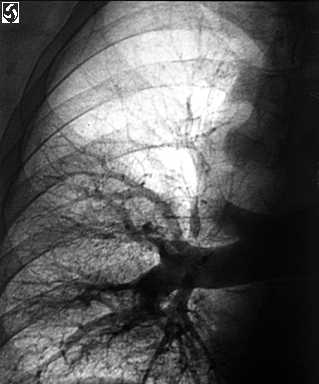

Selectivo derecho pulmonar angiogram

Pulmonar angiography da a conocer una oclusi�n y terminaci�n brusca ( flecha) de la sucursal subir de la arteria pulmonar derecho, el truncus anterior. El relleno de de fallas ( la flecha) est�n presente dentro de las arterias que abastecen los basal segmentos del l�bulo m�s inferior derecho.

La ingle derecho de paciente estuvo dispuesto y tapiz� usando t�cnica est�ril. El Seldinger de t�cnica se us� a percutaneously punzada la derecho com�n femoral la vena con un 18 indicador separa - tapiada de aguja. Un 7 Franc�s pigtail catheter se puso en el inferior vena cava sobre un J-guide el est�ndard cable. El cable se quit�. Un yodo alto (350 mg/ml) nonionic contrasta de medio se infundi� en el catheter y un inferior venacavagram mostrado que el cava estuvo sin thrombus. El catheter se dirigi� mediante el atrio derecho, ventr�culo derecho, extensi�n pulmonar de efusi�n, y arteria pulmonar principal. Las grabaciones de presi�n dadas a conocer una levemente elev� la presi�n principal de arteria pulmonar (37/15 mmHg, significa de 17 mmHg). La presi�n normal de arteria pulmonar era 20-25/8-12 con una significada presi�n de 15. Desde este paciente V/Q repasa mostr� pulm�n predominantemente derecho perfusion fallas, la substracci�n digital selectiva angiography del pulm�n derecho se desempe��. Los derecho pulmonar arteriogram los im�genes mostraron cesaci�n brusco del truncus anterior por occlusive thrombus. Hab�a tambi�n intraluminal fallas de relleno dentro de basilar arterias l�bulo a la derecha m�s inferior. Estos hallazgos proveyeron diagn�stico definitivo de PE.